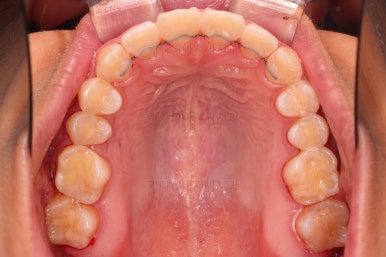

1. 초진 시 입안의 모습 평가

부산연산역치아교정 키다리아저씨치과에 처음 내원했을 당시의 입안의 모습이비다.

앞니 약간, 어금니쪽 약간 삐뚤어진 것, 그리고 위아래 앞니가 약간 뻗쳐 보이는 양상 이외에는 매우 가지런해 보여서 교정치료를 굳이 왜 하시려고 하지? 라고 생각될 정도의 치열 상태였습니다.